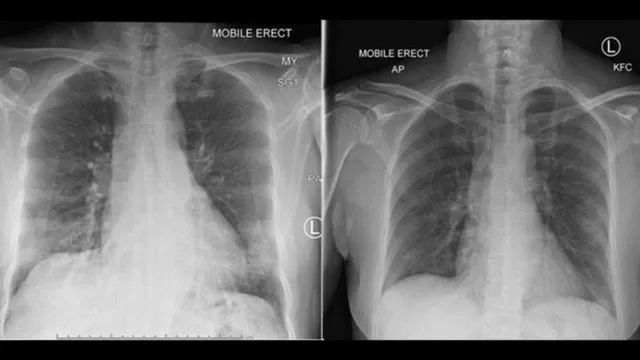

“白肺”,这个经常出现在“新冠肺炎”疫情中的词语,其实这个是指在X光检查下肺部显影呈大片白色状。出现“白肺”,一般意味着肺部有严重感染。

其实,新型冠状病毒肺炎的患者胸部CT或胸片不都是“白肺”,在患病初期,双肺的CT显示正常,但随着疾病发展,若没有得到治疗,肺部便会出现病变加重,也就是俗称“磨玻璃”影。

人的肺就像是二个气囊,在X线下照射,因为密度低,X光穿透性较好,所以在片子上显示是黑色的,“白肺”则是肺部出现严重感染后,肺部充血,渗出及炎性细胞浸润,

密度变高,这才导致双肺X光穿透性较差。